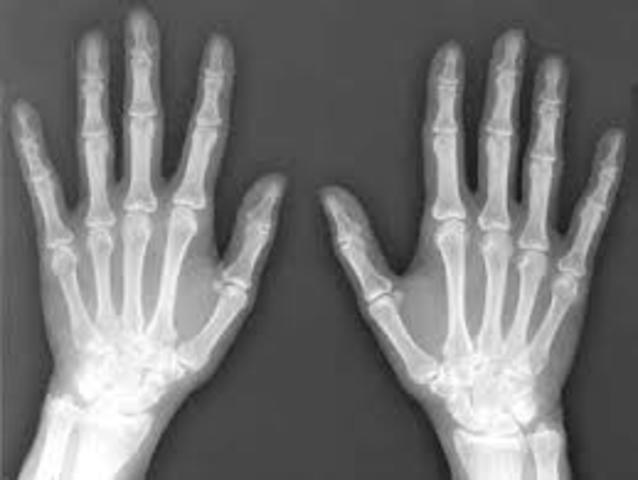

• Welhelm Conrad

Welhelm Conrad

He discovered the medical use of x-rays in medical imaging